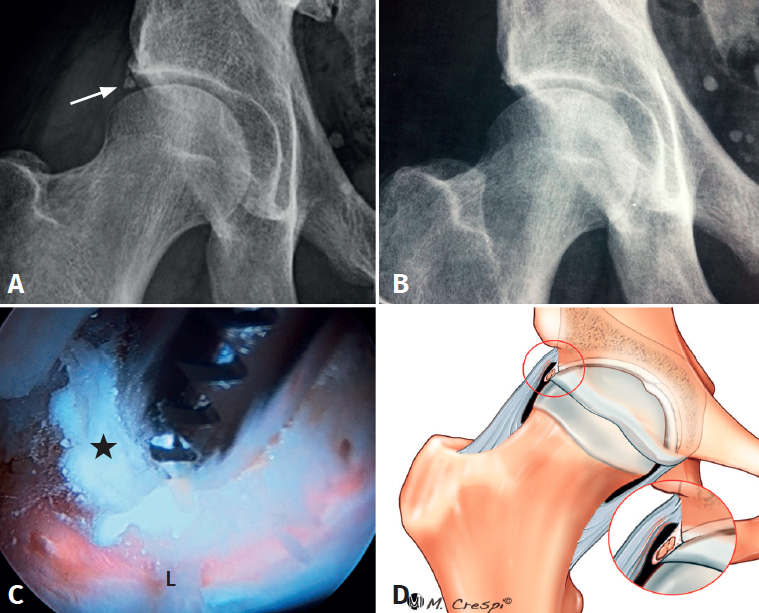

(A2) Calcificaciones grandes y redondeadas: os acetabuli

- Características y morfología radiográfica: gran tamaño, forma redondeada u ovoide, situadas ligeramente a distancia del acetábulo y separadas en relación con el techo acetabular por una línea radiolúcida oblicua u horizontal (Figura 2).

- Localización y lesiones asociadas: predominantemente anterolateral, puede ser bilateral y, al igual que el tipo A1, suele asociar morfología de CFA.

- Tratamiento: este tipo de calcificación se puede reducir o extirpar mediante fresa o en algunos casos extraer con una pinza de tipo grasper como un cuerpo libre tras diseccionarla y separarla cuidadosamente con radiofrecuencia, bisturí y sinoviotomo. A continuación, se debe proceder a la reparación labral del labrum subyacente y, en caso de daño importante o funcionalidad escasa tras la extirpación, complementarlo con una reconstrucción o una aumentación labral.

(A3) Fragmentos grandes con una línea vertical en el borde acetabular superior-lateral compatible con fracturas por estrés consolidadas o no consolidadas

- Características y morfología radiográfica: tamaño grande y línea de fractura perpendicular o vertical en relación con el techo acetabular (Figura 3).

- Localización y lesiones asociadas: generalmente, medio lateral o ligeramente posterior en relación con el acetábulo y también con morfologías de CFA asociadas.

- Tratamiento: dependiendo de la cobertura que quede tras la extirpación, se decidirá si enuclear el fragmento o fijarlo. La planificación preoperatoria es por tanto crucial para garantizar que la escisión de la fractura/fragmento no dé como resultado una cobertura insuficiente o una inestabilidad iatrogénica. La medición del ángulo centro borde lateral y anterior al nivel de la extirpación planificada puede dar una indicación de una cobertura insuficiente resultante si el fragmento contribuye a la estabilidad de la cadera. En estos casos, debe considerarse la fijación quirúrgica mediante fijación con tornillo canulado asistida por artroscopia a través de la unión fibrocartilaginosa(4). En casos de fragmentos grandes que contribuyan simultáneamente al pinzamiento y la estabilidad, se puede realizar resección parcial y fijación del remanente. La utilización de una sutura sobre el tornillo de fijación ayudará a realizar la fijación labral sin tener que usar un arpón o anclaje(4)(Figura 4).